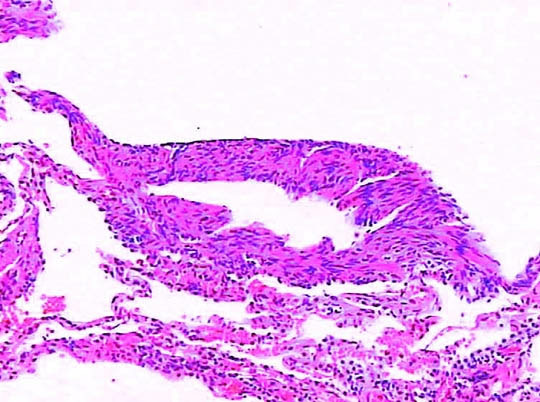

乳糜胸可分为先天性和创伤性(医源性、非医源性、自发性)两类,以外伤性和医源性损伤较常见。

(二)发病机制

当胸导管受压或堵塞时,管内压力增高致导管或其在纵隔内分支破裂,乳糜液反流、溢出而进入纵隔,继之穿破纵隔进入胸腔,形成乳糜性胸腔积液。也有可能因胸导管压力高,发生肺内及肋间淋巴管的扩张、反流,乳糜液不经纵隔而直接漏入胸腔,由于解剖上的原因,阻塞或压迫发生在第五胸椎以下时,仅出现右侧乳糜胸,在第五胸椎以上时,则出现双侧乳糜胸。